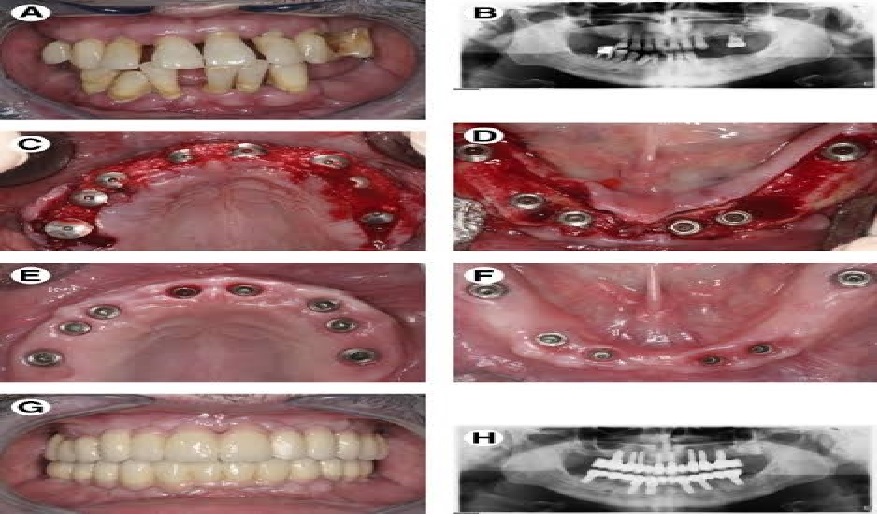

Full fixed Implants

Technically, full mouth dental implant is a procedure that replaces the entire set of teeth from your upper jaw, lower jaw, or both. A set of implants is anchored and prostheses are loaded to bring back your strong natural look of teeth. You can choose to go with the replacement of your upper arch, lower arch or full mouth dental implant.